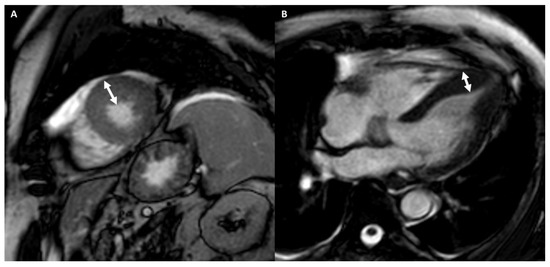

4.2.2. Cardiac Imaging: AH vs. Dilated Cardiomyopathy

4.2.3. Cardiac Imaging: AH vs. Left Ventricular Non-Compaction

- Pradella, S.; Grazzini, G.; De Amicis, C.; Letteriello, M.; Acquafresca, M.; Miele, V. Cardiac magnetic resonance in hypertrophic and dilated cardiomyopathies. Radiol. Med. 2020, 125, 1056–1071. [Google Scholar] [CrossRef] [PubMed]